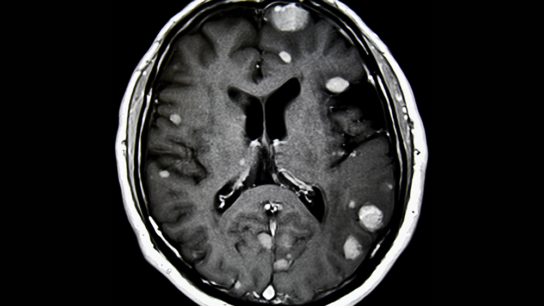

The combination of nivolumab with ipilimumab is an effective treatment option for patients with advanced melanoma with asymptomatic brain metastases

Occult brain metastasis is identified in about 4 percent of patients with metastatic renal cell carcinoma (mRCC).